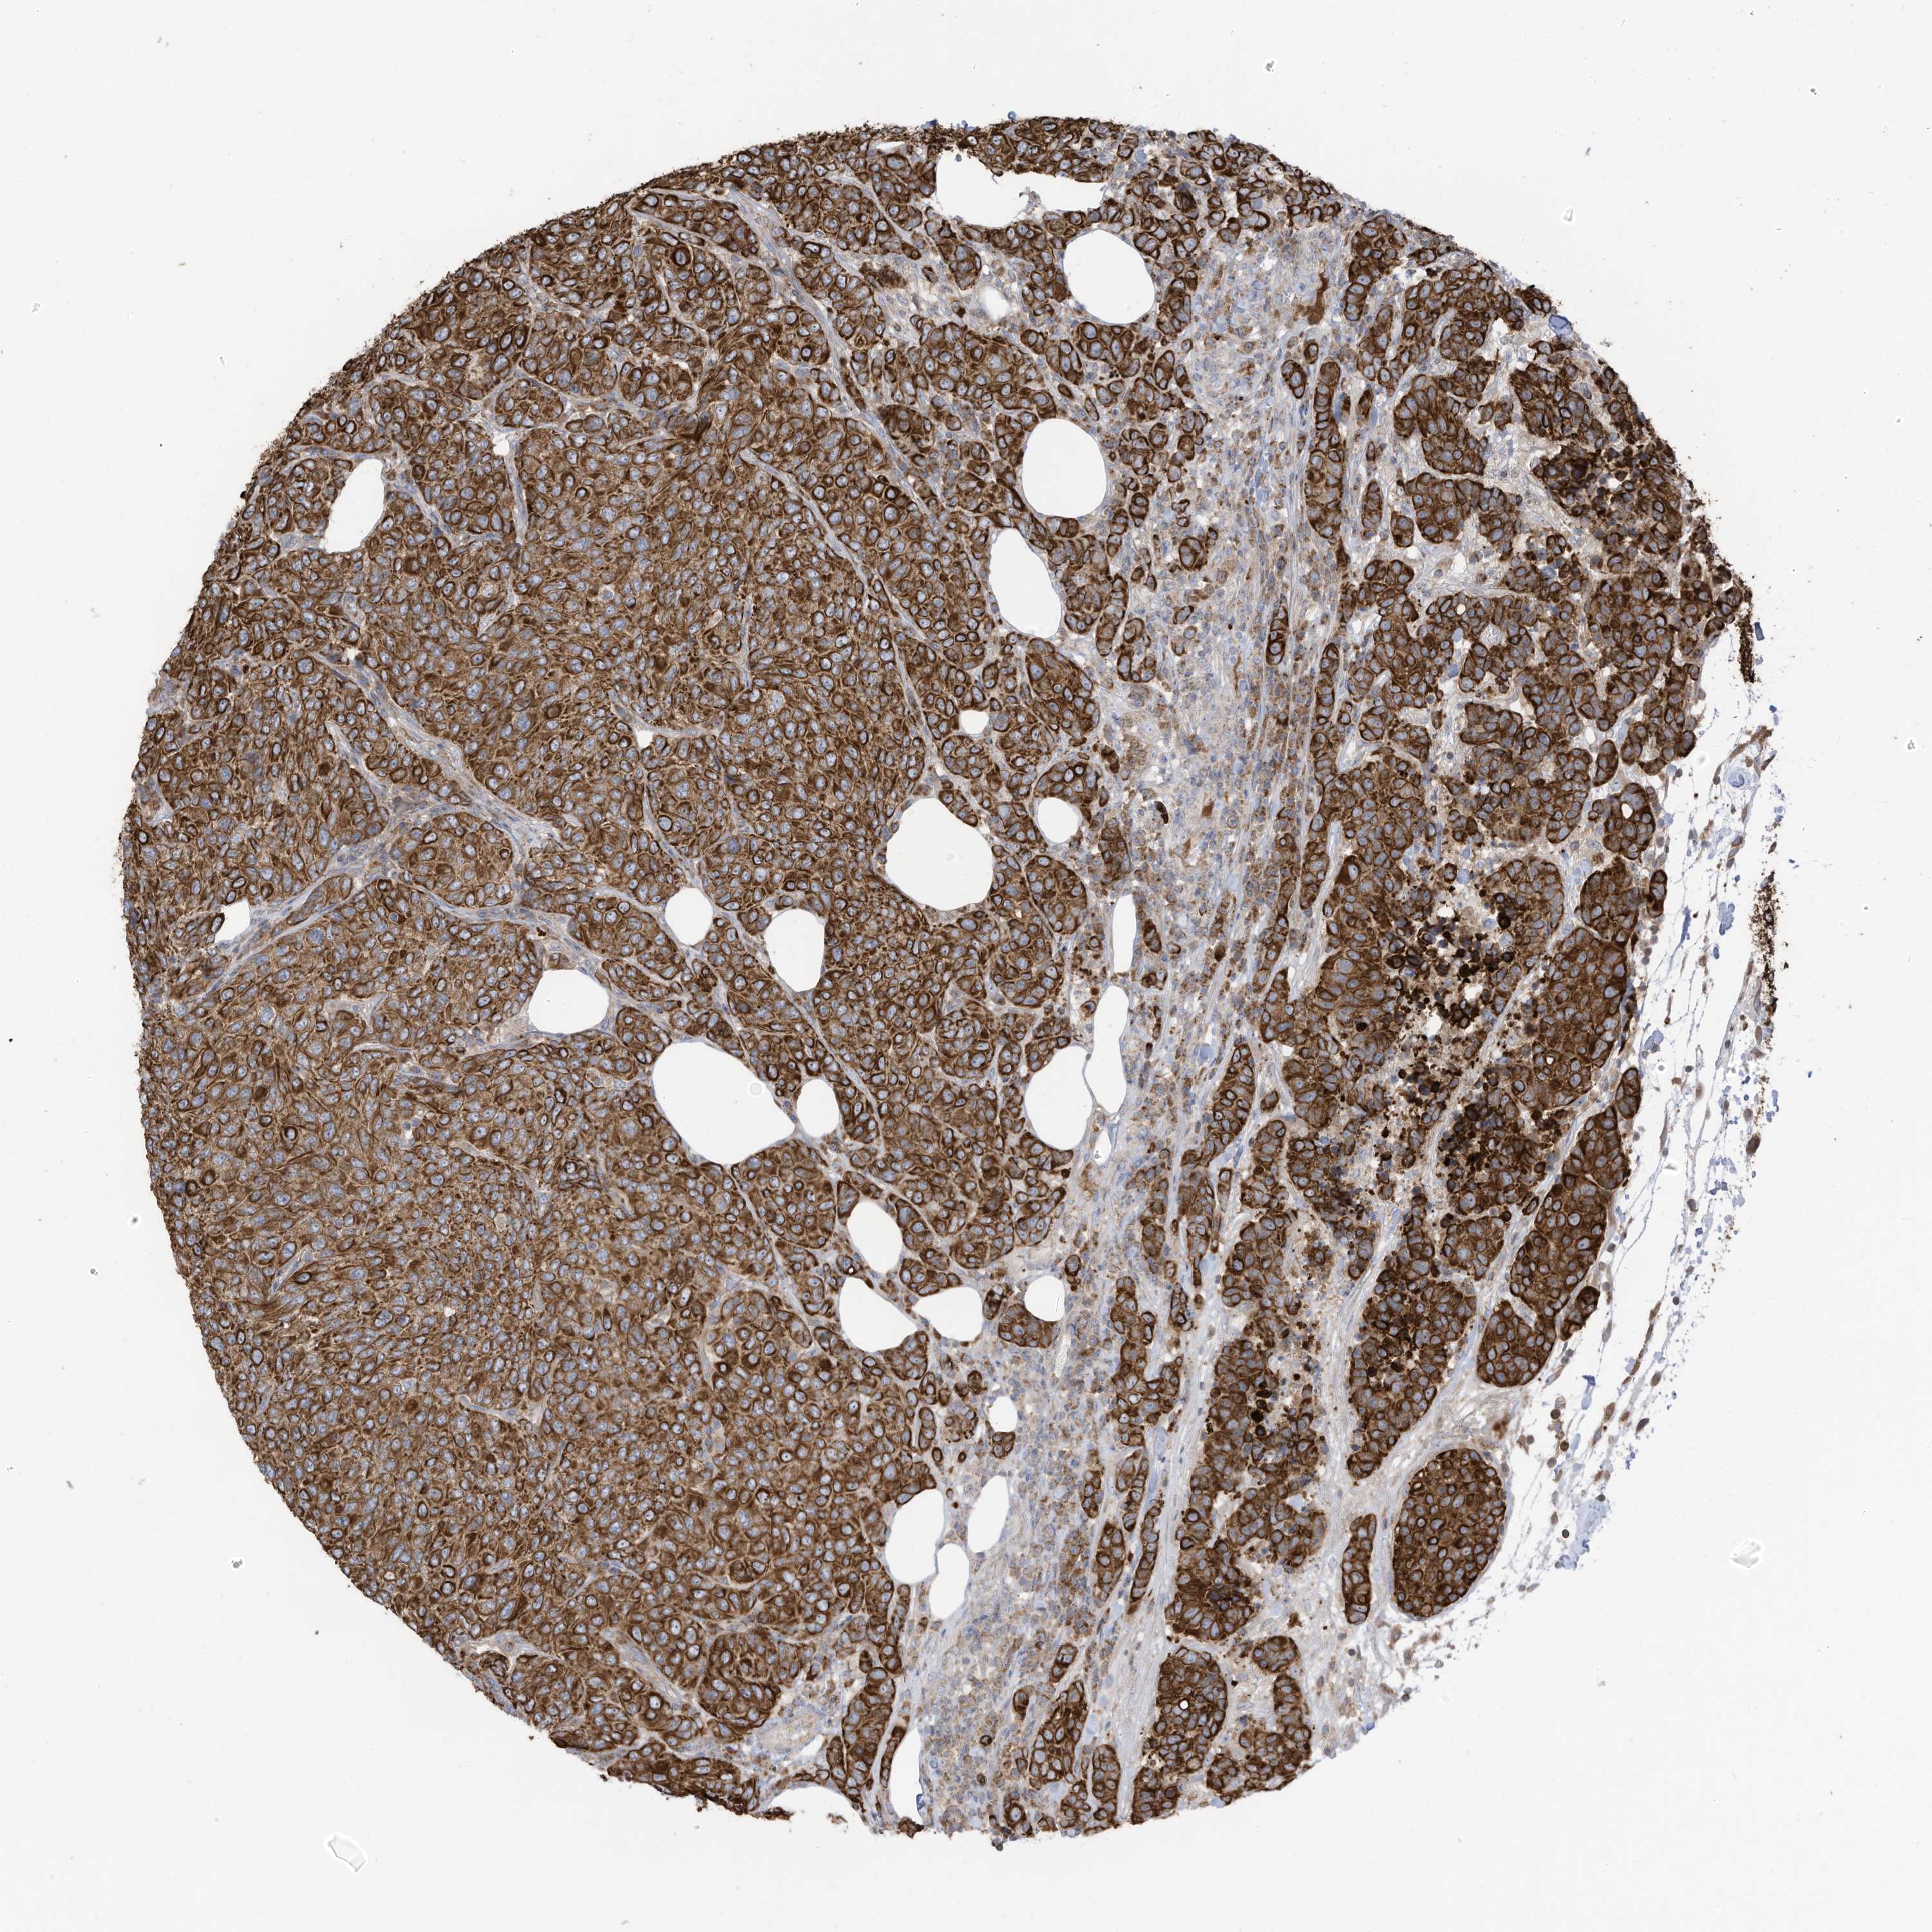

CANCER BREAST CANCER Show tissue menu

BRCA TCGA BRCA VALIDATION PROTEIN EXPRESSION